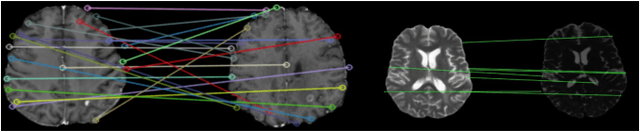

Abstract:Graph neural networks (GNNs) present a promising alternative to CNNs and transformers in certain image processing applications due to their parameter-efficiency in modeling spatial relationships. Currently, a major area of research involves the converting non-graph input data for GNN-based models, notably in scenarios where the data originates from images. One approach involves converting images into nodes by identifying significant keypoints within them. Super-Retina, a semi-supervised technique, has been utilized for detecting keypoints in retinal images. However, its limitations lie in the dependency on a small initial set of ground truth keypoints, which is progressively expanded to detect more keypoints. Having encountered difficulties in detecting consistent initial keypoints in brain images using SIFT and LoFTR, we proposed a new approach: radiomic feature-based keypoint detection. Demonstrating the anatomical significance of the detected keypoints was achieved by showcasing their efficacy in improving registration processes guided by these keypoints. Subsequently, these keypoints were employed as the ground truth for the keypoint detection method (LK-SuperRetina). Furthermore, the study showcases the application of GNNs in image matching, highlighting their superior performance in terms of both the number of good matches and confidence scores. This research sets the stage for expanding GNN applications into various other applications, including but not limited to image classification, segmentation, and registration.